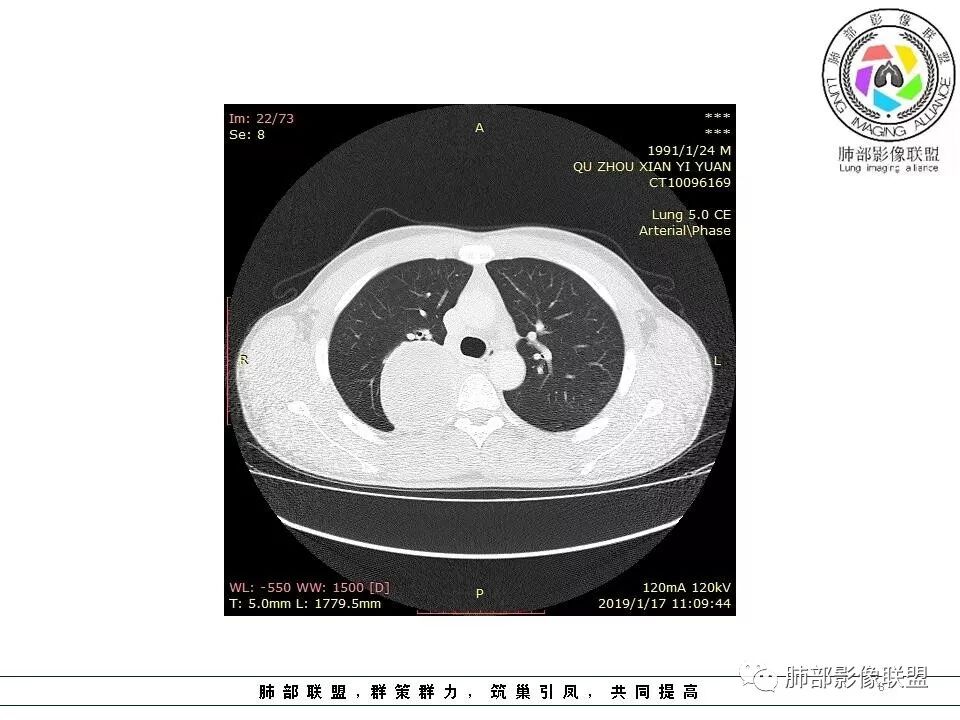

右肺占位,跨越上叶后段、下叶背,边缘光滑,瘤肺界面清,见肺压缩缘(线样不张`强化),见胸膜尾征,胸膜下脂肪未见明显增厚,肋骨丶脊柱未见侵袭及受压,渐进性丶地图样强化,冠状位似见体循环供血

边缘光滑,宽基底与胸壁相连,跨叶裂,叶裂稍前推,血管、支气管前移。

浅分叶

外上侧少量胸水

肋间动脉供血,强化尚均匀,逐步强化

3.相邻椎间孔未见扩大,也未见块影延入椎管,易起自于神经根的鞘瘤似乎找不到支持点。

可惜未提供矢状位骨窗图像,如在肋骨内下缘观察到压迹有助于肋间神经的鞘瘤的判断,这是因为二者之间密切的毗邻关系。